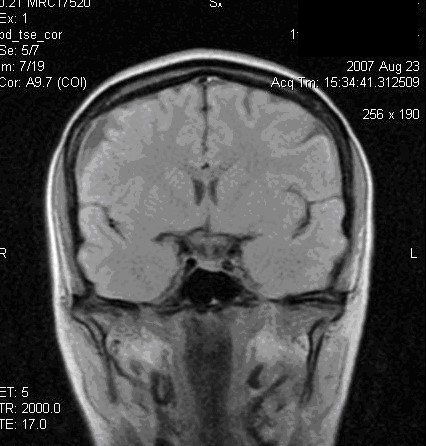

При изучении структур мозги МРТ имеет некоторые преимущества перед КТВо-первых, на MP-томограммах более четко различаются структурные элементы головного мозга, отчетливее дифференцируются белое и серое вещество, все стволовые структуры. На качестве магнитно-резонансных то­мограмм не отражается экранирующее действие костей черепа, ухудшаю­щее качество изображения при КТ. Во-вторых, МРТ можно производить в разных проекциях и получать не только аксиальные, как при КТ, но и фронтальные, сагиттальные и косые слои. В-третьих, это исследование не связано с лучевой нагрузкой. Особым достоинством МРТ является возмож­ность отображения сосудов, в частности сосудов шеи и основания головно­го мозга, а при контрастировании гадолинием -- и мелких сосудистых вет­вей (см. рис. 35 и 36).

Рис. 35.         МРТ изображения  области головы в сагиттальной и фронтальной плоскостях Т1 ВИ,  хорошо различимы структуры головного мозга.